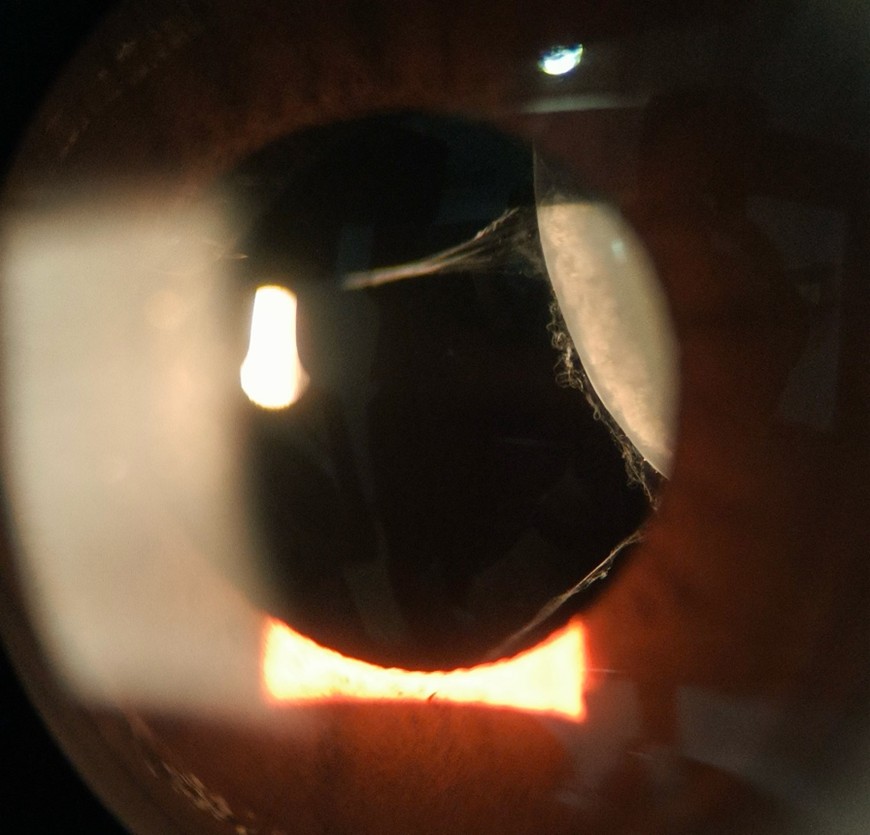

These photos show a rarely reported phenomenon: endocapsular hematoma. Traumatic hyphema trapped behind an intraocular lens in the capsular bag, forming a blood-fluid level. Due to a lack of improvement on observation, it required surgical intervention to open and irrigate the posterior capsular space.

“Ophthalmologists and optometrists often diagnose and manage hyphemas in the anterior chamber, but in this case, the blood had migrated into the capsular bag posterior to the intraocular lens implant. This is an anatomic space that is normally empty, but in this case, the blood had become trapped until definitive intervention,” said Dr. Sethi about the image. “Not only is the blood-fluid level visually stunning, but it’s a great example of how management has to be deliberate and patient-specific.”

“Ophthalmology gives us a front-row view to rare anatomy and pathology that is truly mesmerizing under the view of a slit lamp microscope,” he continued. “Images like this are a reminder to pause and appreciate what we see every day in our daily work toward restoring vision.”